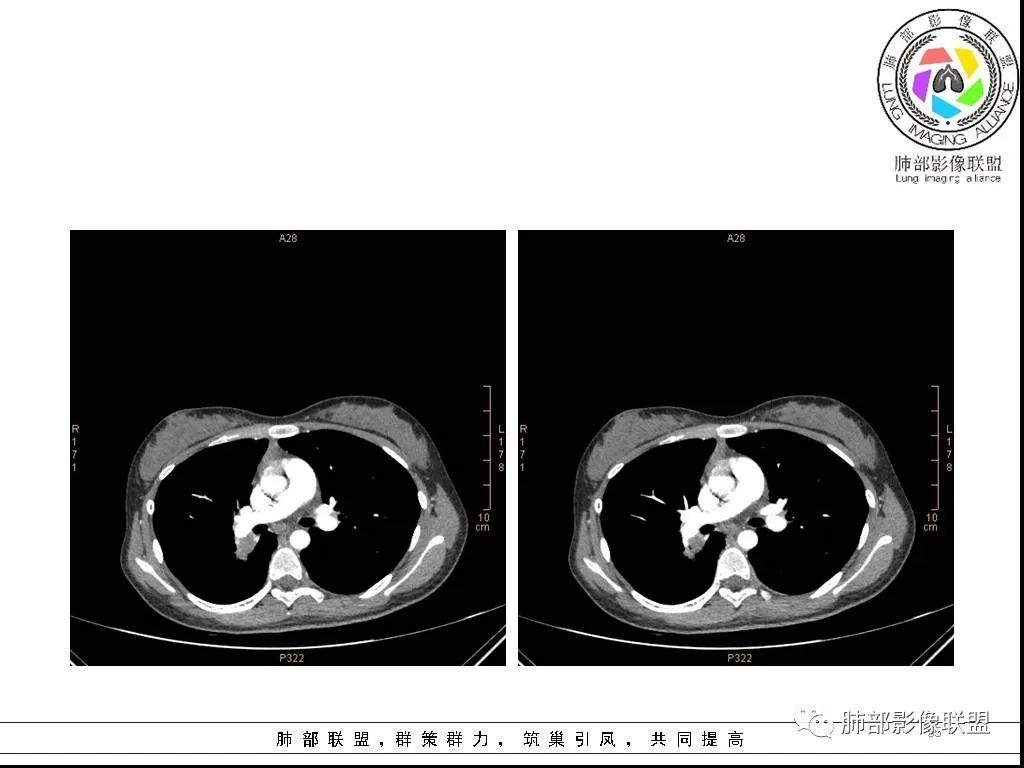

右肺炎症性病变1例CT影像讨论

年轻女性,病程长,咳嗽少痰4个月,辅检未见特殊,CT:右肺团块影,跨叶,主体在下叶背段,外大内小,边缘以膨隆为主,部分平直内收,深分叶,周围有模糊晕,可疑卫星灶,胸膜增厚,糊墙,支气管近端部分进入,粘液栓,有坏死空腔,内壁光整,部分血管侵蚀,强化不均,延迟,明显;同侧R10、7、R4淋巴结肿大,考虑肉芽肿炎,结核,需要与肿瘤鉴别:16岁,女性,诊断肿瘤需要勇气,跨叶多见于炎性,需要进一步活检。

16岁女性,咳嗽,咳痰4月,无发热,白细胞不高,炎性指标(CRP,PPT)不高,血沉增高(75mm/h)。影像表现:右肺胸膜下不规则肿块影,边缘平直,U型凹陷,桃尖征为主,纵隔窗部分层面似有多个结节融合感,近端支气管扩张,堵塞,局部呈鬼脸样改变。边缘可见长短不一毛刺影,周围见晕征,远端见多个小结节卫星灶。胸膜大面积反应性增厚,增强后不均匀中度渐进性强化,局部干酪样坏死可能(CT值-32~-15)内部血管走行较正常,破坏不明显。 医学百科网 | YxBaike.Com

综合分析:病灶边缘平直,U型凹陷,桃尖征为主,周围见晕征,远端见多个小结节卫星灶。胸膜大面积反应性增厚,增强后不均匀中度渐进性强化,加上临床的表现,大方向支持炎性肉芽肿。疾病谱:隐球菌,结核,普通感染,OP,淋巴瘤。结合临床与影像表现:初步诊断:隐球菌可能,诊断依据:一是临床症状及检验指标支持,二是胸膜下肿块,边缘平直,U型凹陷,桃尖征为主,周围见晕征,远端见多个小结节卫星灶,胸膜大面积反应性增厚,增强后不均匀中度渐进性强化,局部干酪样坏死,鬼脸征,血管走行较正常,有破坏,但破坏不明显。需要做隐球菌荚膜抗原检查或穿刺活检进一步明确。鉴别诊断:1、结核,破坏力不明显,坏死不明显,收缩力不够强,无树芽征,临床无结核中毒症状,结核抗体阴性,结核感染T细胞阴性,PPD阴性。但有支气管爬行征,血管有破坏支持结核。2、淋巴瘤:增强后血管破坏不明显支持,其他不支持,所以可能性小,但不完全排除。3、普通细菌感染:白细胞,炎症指标,以及抗炎无效,不支持。4、OP:影像表现要考虑慢性炎症恢复期所致OP,但既然前面分析不支持普通感染,再加上病人咳嗽,咳痰症状持续4月不太支持。

这个病例的特点:病灶贴近斜裂内侧区域,范围较大,直达肺门区。右肺上叶,前、尖、后段前移,病灶嵌塞于上叶后段支气管的后下方区域,未能跟踪到病灶与叶段支气管关系。应当怀疑有额外的支气管存在,也就是副叶。因为这么大的病灶,这么粗大肺动脉进入,伴行的支气管应当比较粗大,但是没能观察到较大的支气管与其相延续。

病灶明显是由靠近斜裂这个方向朝肺门侧蔓延的,外围大,内带小,病灶远端没有阻塞的肺组织,伴行的肺动脉是包绕之中的。这不符合肺门区的支气管黏液栓堵塞或肺门区的大肿块(堵塞支气管),它的病灶变化不是这样的。

病灶内部存在管状分布液性低密度区,这与复查显示的柱状管样气腔对应吻合,支持先天性支气管扩张的存在,仅仅是影像未能显示出入口。